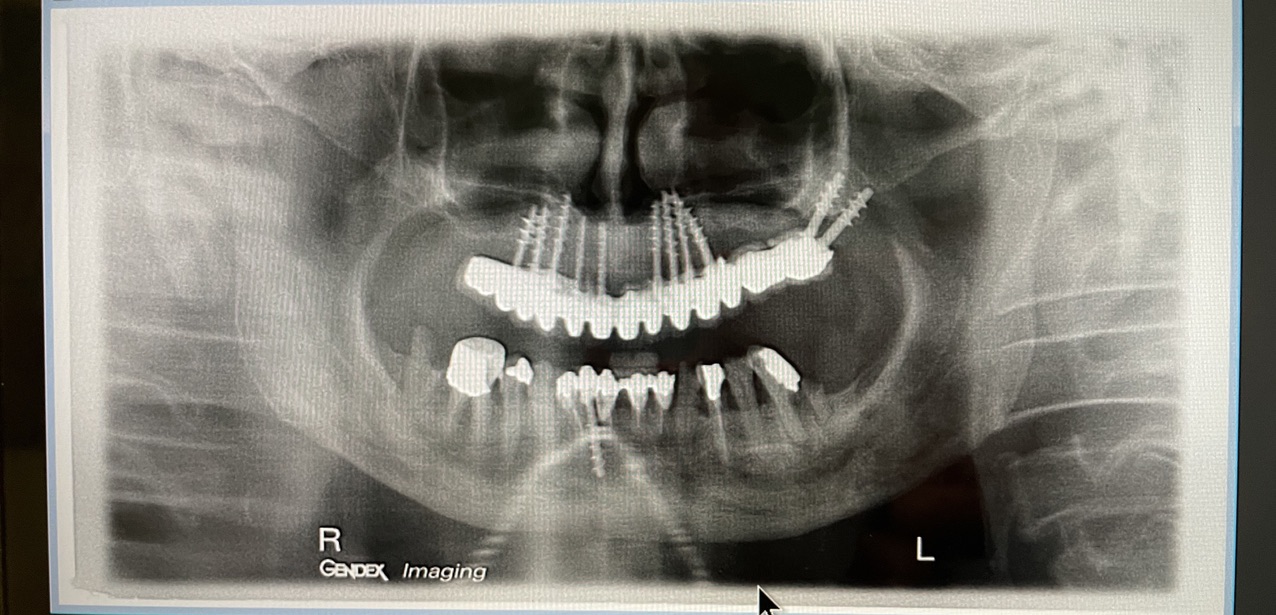

CASO CLINICO : Riabilitazione del 28/04/2021

In particolare considero notevoli i seguenti aspetti:

• 1 età del paziente. 83 anni

• 2 esecuzione dei primi 6 impianti: 25 anni fa

• 3 esecuzione dei 5 impianti successivi: 14 anni fa

• 4 medicinali assunti dal paziente: nessuno

• 5 presenza di impianti in zona tuber/pterigoidea

• 6 presenza di impianti inclinati di antica data

• 7 presenza di impianto piegato in 25. (Per parallelizzarlo)

• 8 presenza di due miniimpianti in 11-12

• 9 presenza di barra saldata nel settore superiore

• 10 grave parodontopatia del settore inferiore

• 11 problematiche igieniche

• 12 insuccesso implantare di impianto di Tramonte inferiore, impianto precedente al 2004, nel quadro della generale parodontopatia

• 13 l’inserimento dei tre impianti non ha comportato innesti di osso o di tessuti connettivali.

• 14 Non ha reso necessari scollamenti

• 15 Non è stata necessario isolare le emergenze dei nervi alveolari inferiori

• 16 Trattandosi di osso ad elevata densità si è ricorsi alla fresa elicoidale, strumento raramente utilizzato da noi perchè non necessario e perchè ci sono zone in cui il suo utilizzo comporta rischi chirurgici per noi non accettabili. Inoltre questa fresa asporta quantità discrete di osso che preferiamo resti dove la natura lo ha messo. Interessante il fatto che il diametro della fresa è di solo 2 mm

• 17 Trattandosi di osso denso, gli impianti utilizzati avevano un diametro di soli 4 mm dopo maschiatura col corrispondente maschiatore.

• 18 Al controllo del 3/5/2021 il paziente non è gonfio e riferisce che mangia finalmente bene.

• 19 Inizio intervento implantare alle 8.45. fine intervento implantare alle 9.36.

• 20 Cementazione del provvisorio, confezionato al momento, ultimata alle 10.30. durata totale permanenza del paziente in ambulatorio1,45 ore.

Le immagini forniscono nelle didascalie ulteriori informazioni.